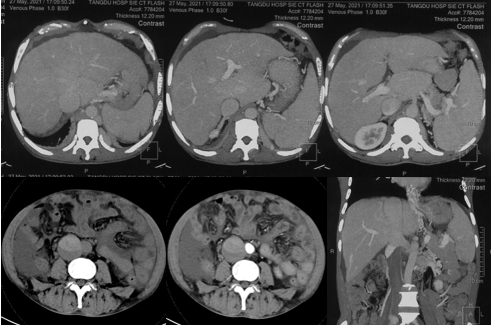

6月20日,患者及家屬懷揣著忐忑的心情來到西安國際醫(yī)學(xué)中心醫(yī)院找到韓國宏教授,韓教授詢問病情后閱患者外院CT片,明確診斷布加綜合征,同時發(fā)現(xiàn)了一個新的問題,在詢問病史時了解到患者近一周雙下肢乏力伴腫脹明顯加重,遂立即安排了急診CT,證實(shí)下腔靜脈內(nèi)急性血栓形成!

6月22日,在韓國宏教授的帶領(lǐng)下,患者于消化介入診療中心行下腔靜脈開通術(shù)。術(shù)中可見:下腔靜脈全段擴(kuò)張,膜性閉塞,腎靜脈平面以下可見血栓形成并伴有粗大的側(cè)枝靜脈,遂對狹窄段球囊擴(kuò)張并植入支架,術(shù)后下腔靜脈血流通暢,側(cè)枝消失。術(shù)后第2天,患者腹壁靜脈曲張幾乎消失不見,走路也輕快了許多。明明只是薄薄的一層膜,為什么開通起來這么難?韓教授指出,盡管布加綜合征介入開通技術(shù)已使創(chuàng)傷降到了最低,但受到患者個體差異及醫(yī)療水平參差不齊的限制,仍有可能出現(xiàn)嚴(yán)重的并發(fā)癥,主要包括:心包積血、縱隔血腫、心包填塞甚至下腔靜脈撕裂引起的大出血等。而其發(fā)生率與術(shù)者的操作熟練程度及經(jīng)驗(yàn)有很大的關(guān)系。